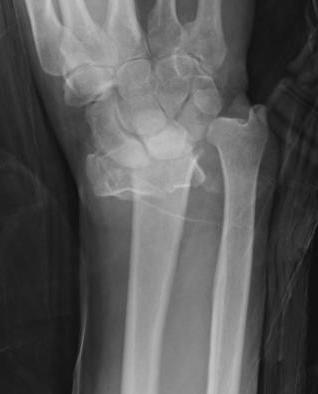

Distal radius fracture with shortening and dorsal tilt

Articular incongruency > 2 mm

Sigmoid notch disruption and DRUJ instability